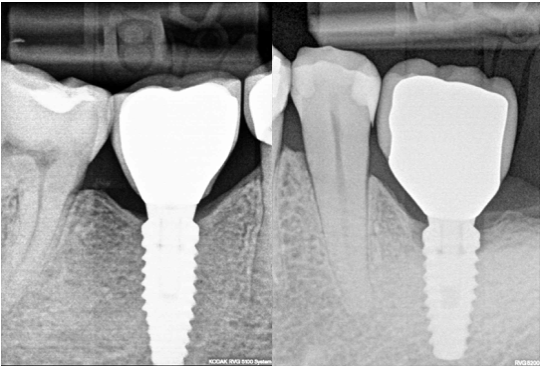

On the other hand, let’s admit, that all of us would choose Fig 1 A implant, without bone loss, and not Fig 1B implant, although the difference is very small. Sometimes clinicians tend to downplay this bone loss because simply they do not understand, why the bone is disappearing, and are not eager to learn.

Screenshot at ..

Fig. 1 (A and B)